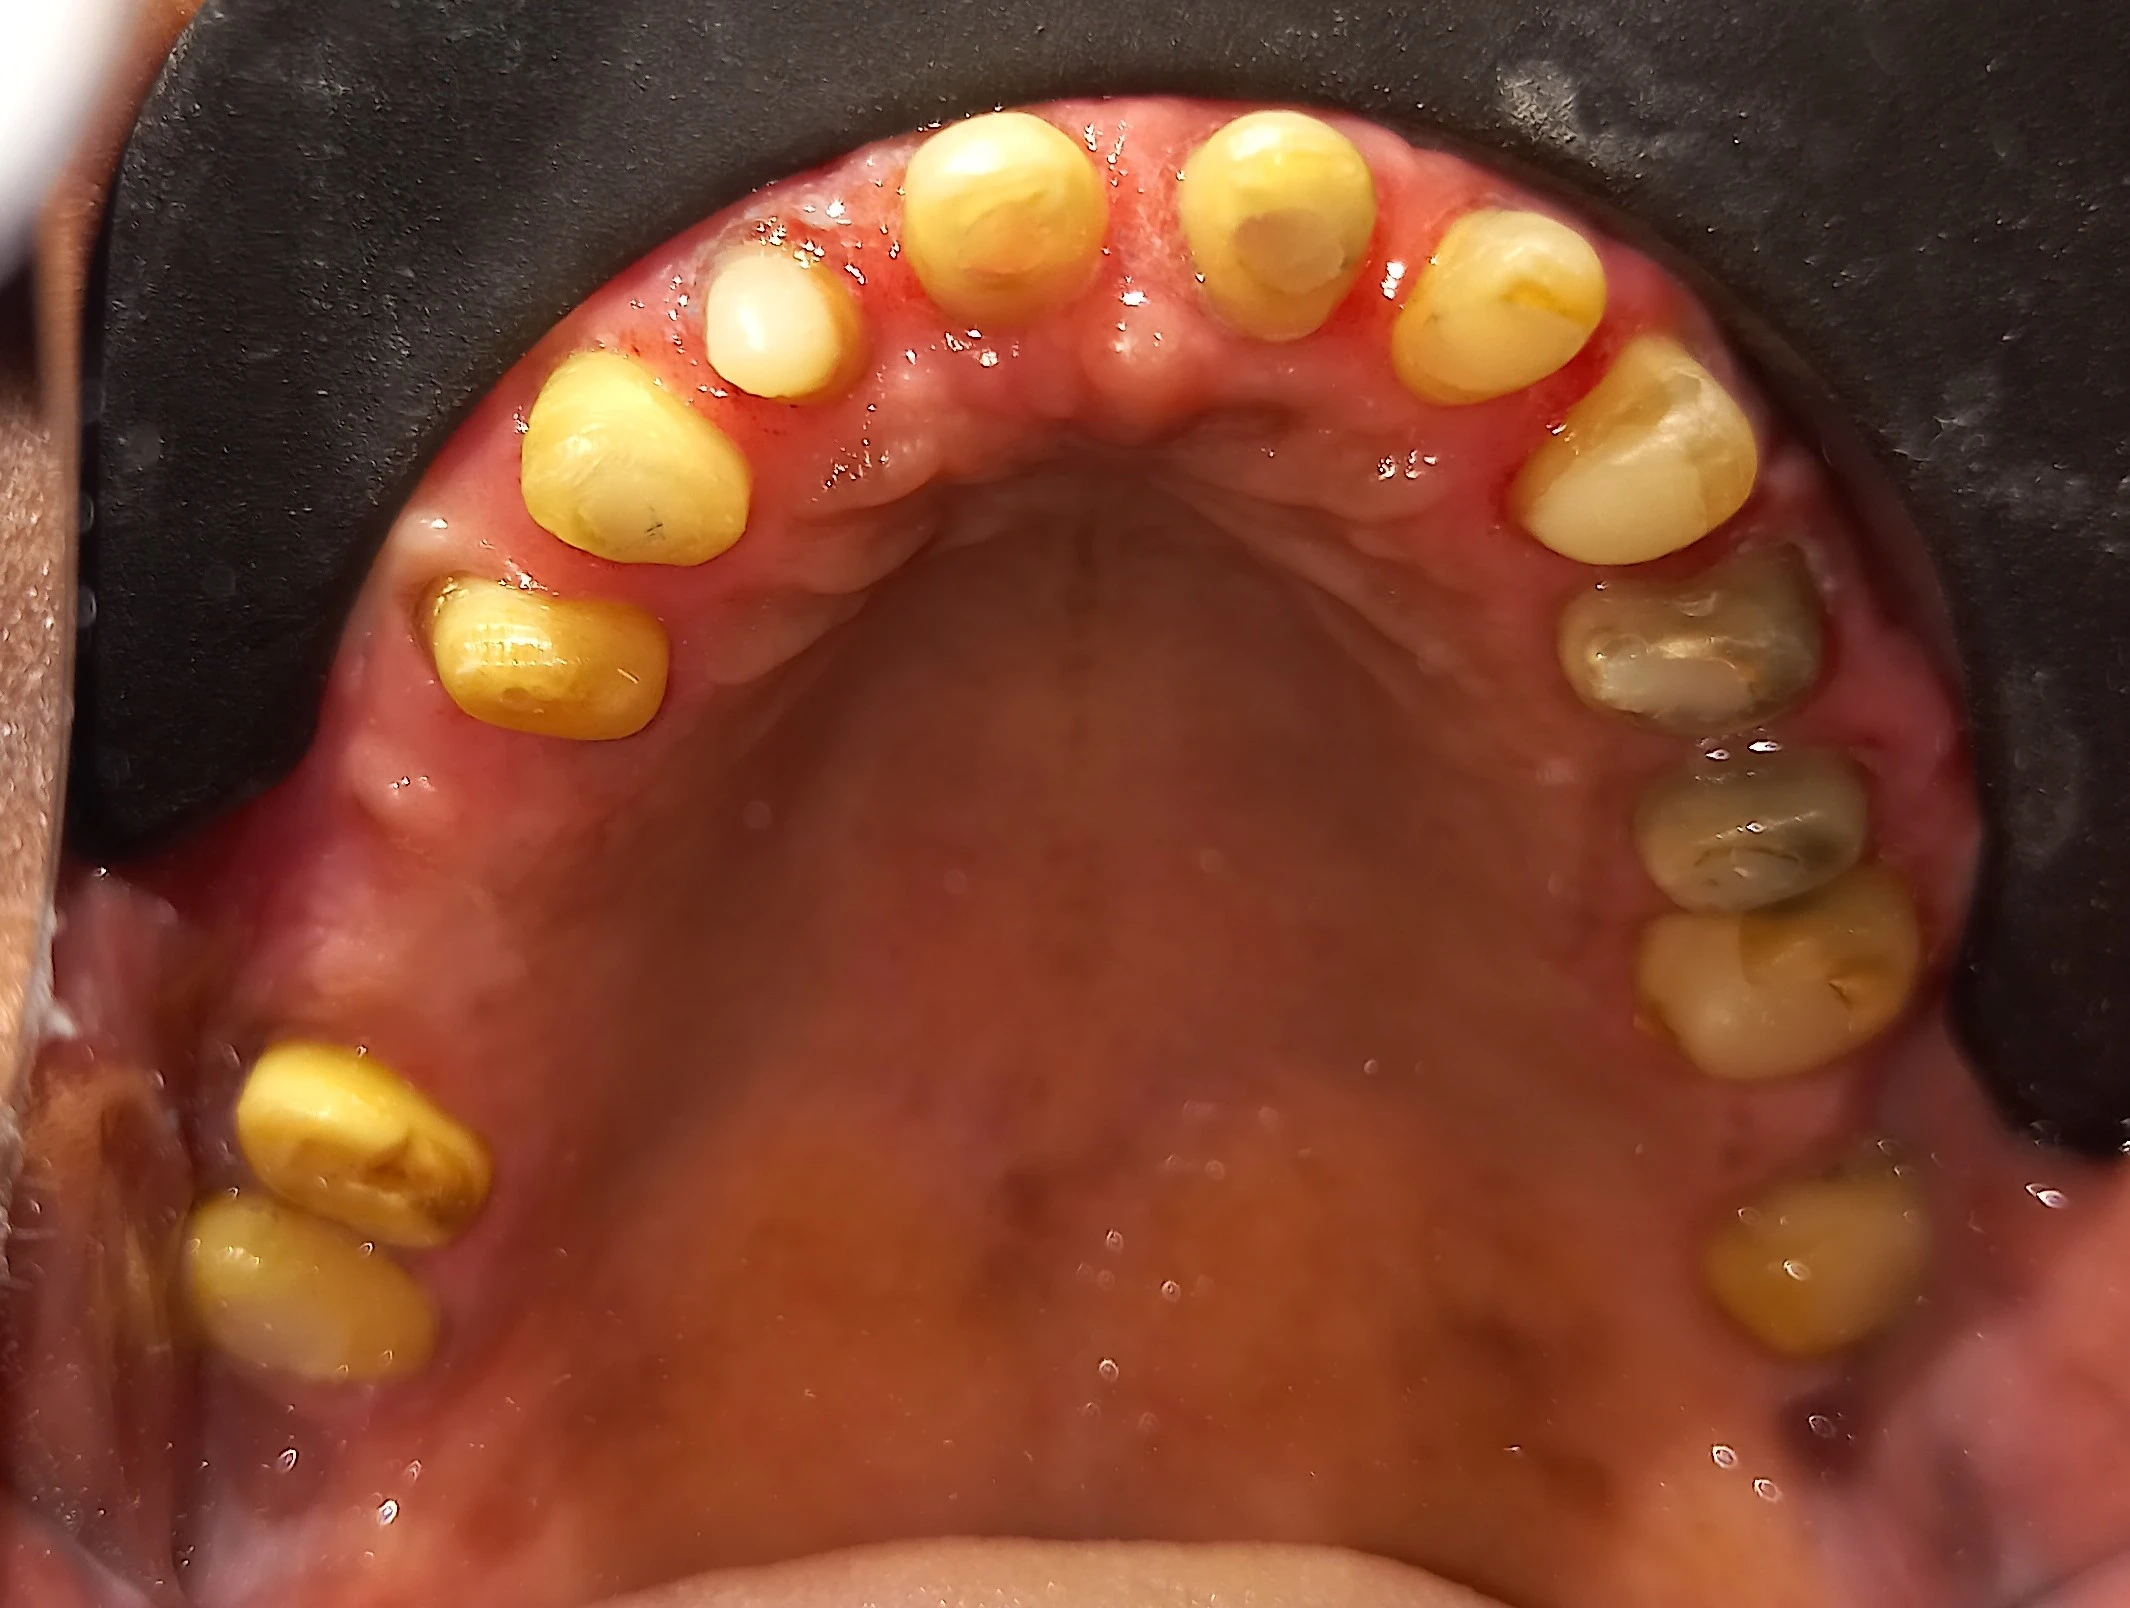

This young patient had almost all teeth worn down due to a faulty bite. She was advised elsewhere to undergo root canal treatment on all teeth followed by crowns.

However, after detailed bite measurements, jaw analysis, and mock planning, it was clear that most teeth were healthy but over-worn. Root canal treatment was required only for 2–3 teeth.

The remaining teeth were carefully reshaped, tested for sensitivity, and protected using precisely designed crowns — avoiding unnecessary procedures.

This decision is possible only after bite analysis and prosthodontic planning — not by looking at X-rays alone.

Worn teeth due to faulty bite before treatment

Before treatment: severely worn teeth due to faulty bite